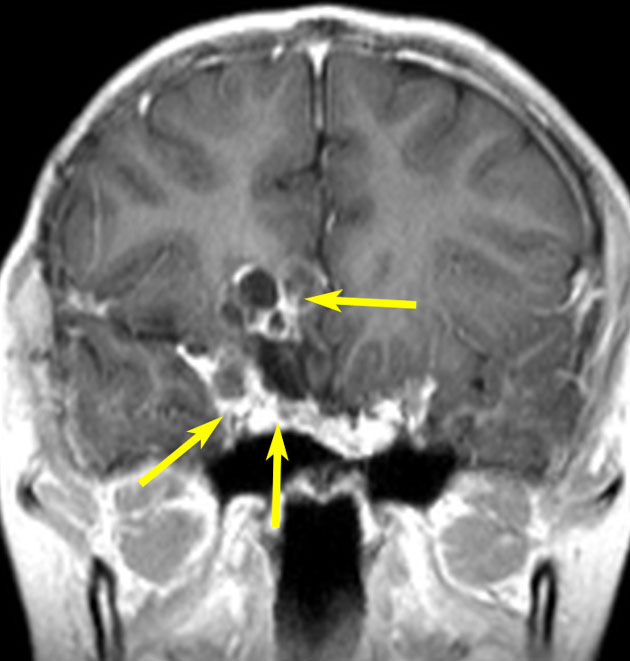

第3脳室内のadamantinomatous craniopharyngiomaです。これを両側前頭開頭,経脳梁法 transcallosall approachで摘出しました。下垂体と下垂体柄を温存するためです。

初回手術から6年後,原発部位に腫瘍はありません。しかし,前頭部大脳鎌(赤矢印)に腫瘍が発生しました。これは手術経路(緑の線)に沿った位置にあるので,drop metastasisだとわかりました。病理は初回と同じものです。このdrop metastasisは意外に多いものです。頭蓋咽頭腫は,極小の腫瘍片でも脳表や脳槽にこぼれ落ちれば,そこで着床して,数年後に再発となって現れるということを示しています。ですから,手術の時に断片を残したり落としたりしてはなりません。